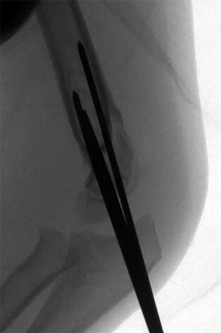

A 13-year-old obese male with a stable left Slipped Capital Femoral Epiphysis (SCFE) undergoes in situ pinning with a single cannulated screw.

Six months postoperatively, he develops severe, constant hip pain and a significantly restricted range of motion in all planes. Radiographs demonstrate concentric joint space narrowing without hardware failure. What is the most likely diagnosis?